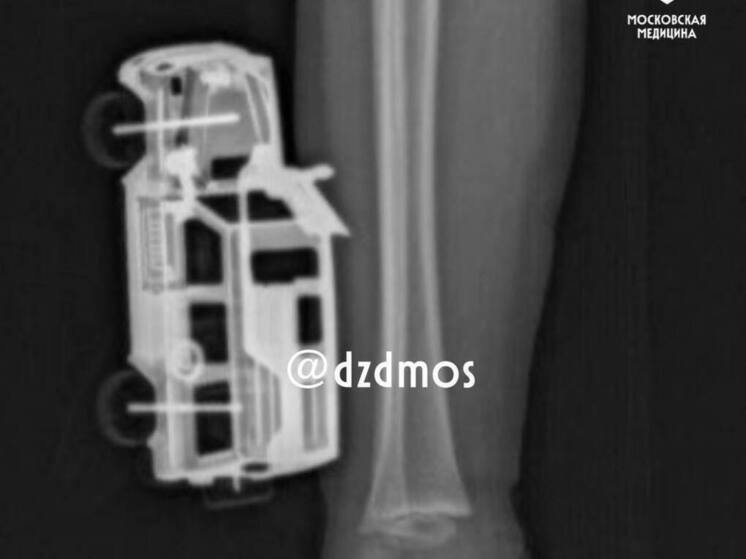

Извлекать из ноги четырехлетнего пациента игрушечную машинку пришлось врачам детской больницы имени Сперанского.

Как сообщили «МК» в Департаменте здравоохранения столицы, малыш неудачно прыгнул с кровати прямо на металлическую машинку. Игрушка повредила мягкие ткани правой  ноги и впилась в голень так, что самостоятельно ее извлечь было невозможно.

Медики удалили игрушку и выполнили хирургическую обработку серьезной раны. Спустя сутки малыша выписали домой.